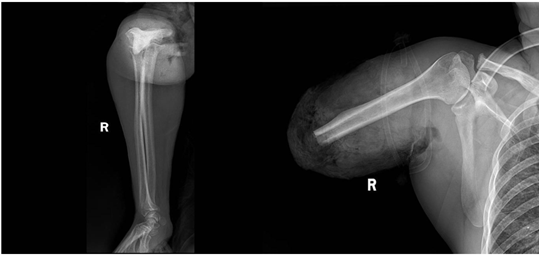

后经完善CT等相关检查发现,患者右上臂中上段已全部离断,局部皮肤脱套,肩部至前臂软组织均存在严重挫伤,重要的血管神经断裂并形成缺损,且右侧胸壁有多处软组织严重挫伤积气、肺挫裂伤、多发性肋骨骨折等严重危及患者生命的合并伤。

由于患者右上臂离断组织严重挫伤,各种复杂的组织修复与重建需要耗费大量时间,在麻醉科、输血科、手术室等多学科的协助下,急诊科凌裕、李艺龙两位医生密切配合,精确地对患者的每一根血管进行吻合桥接,修复重建肌肉,并对右上臂进行血运复通……经过11个小时的紧张救治,团队顺利完成患者断臂的再植手术。